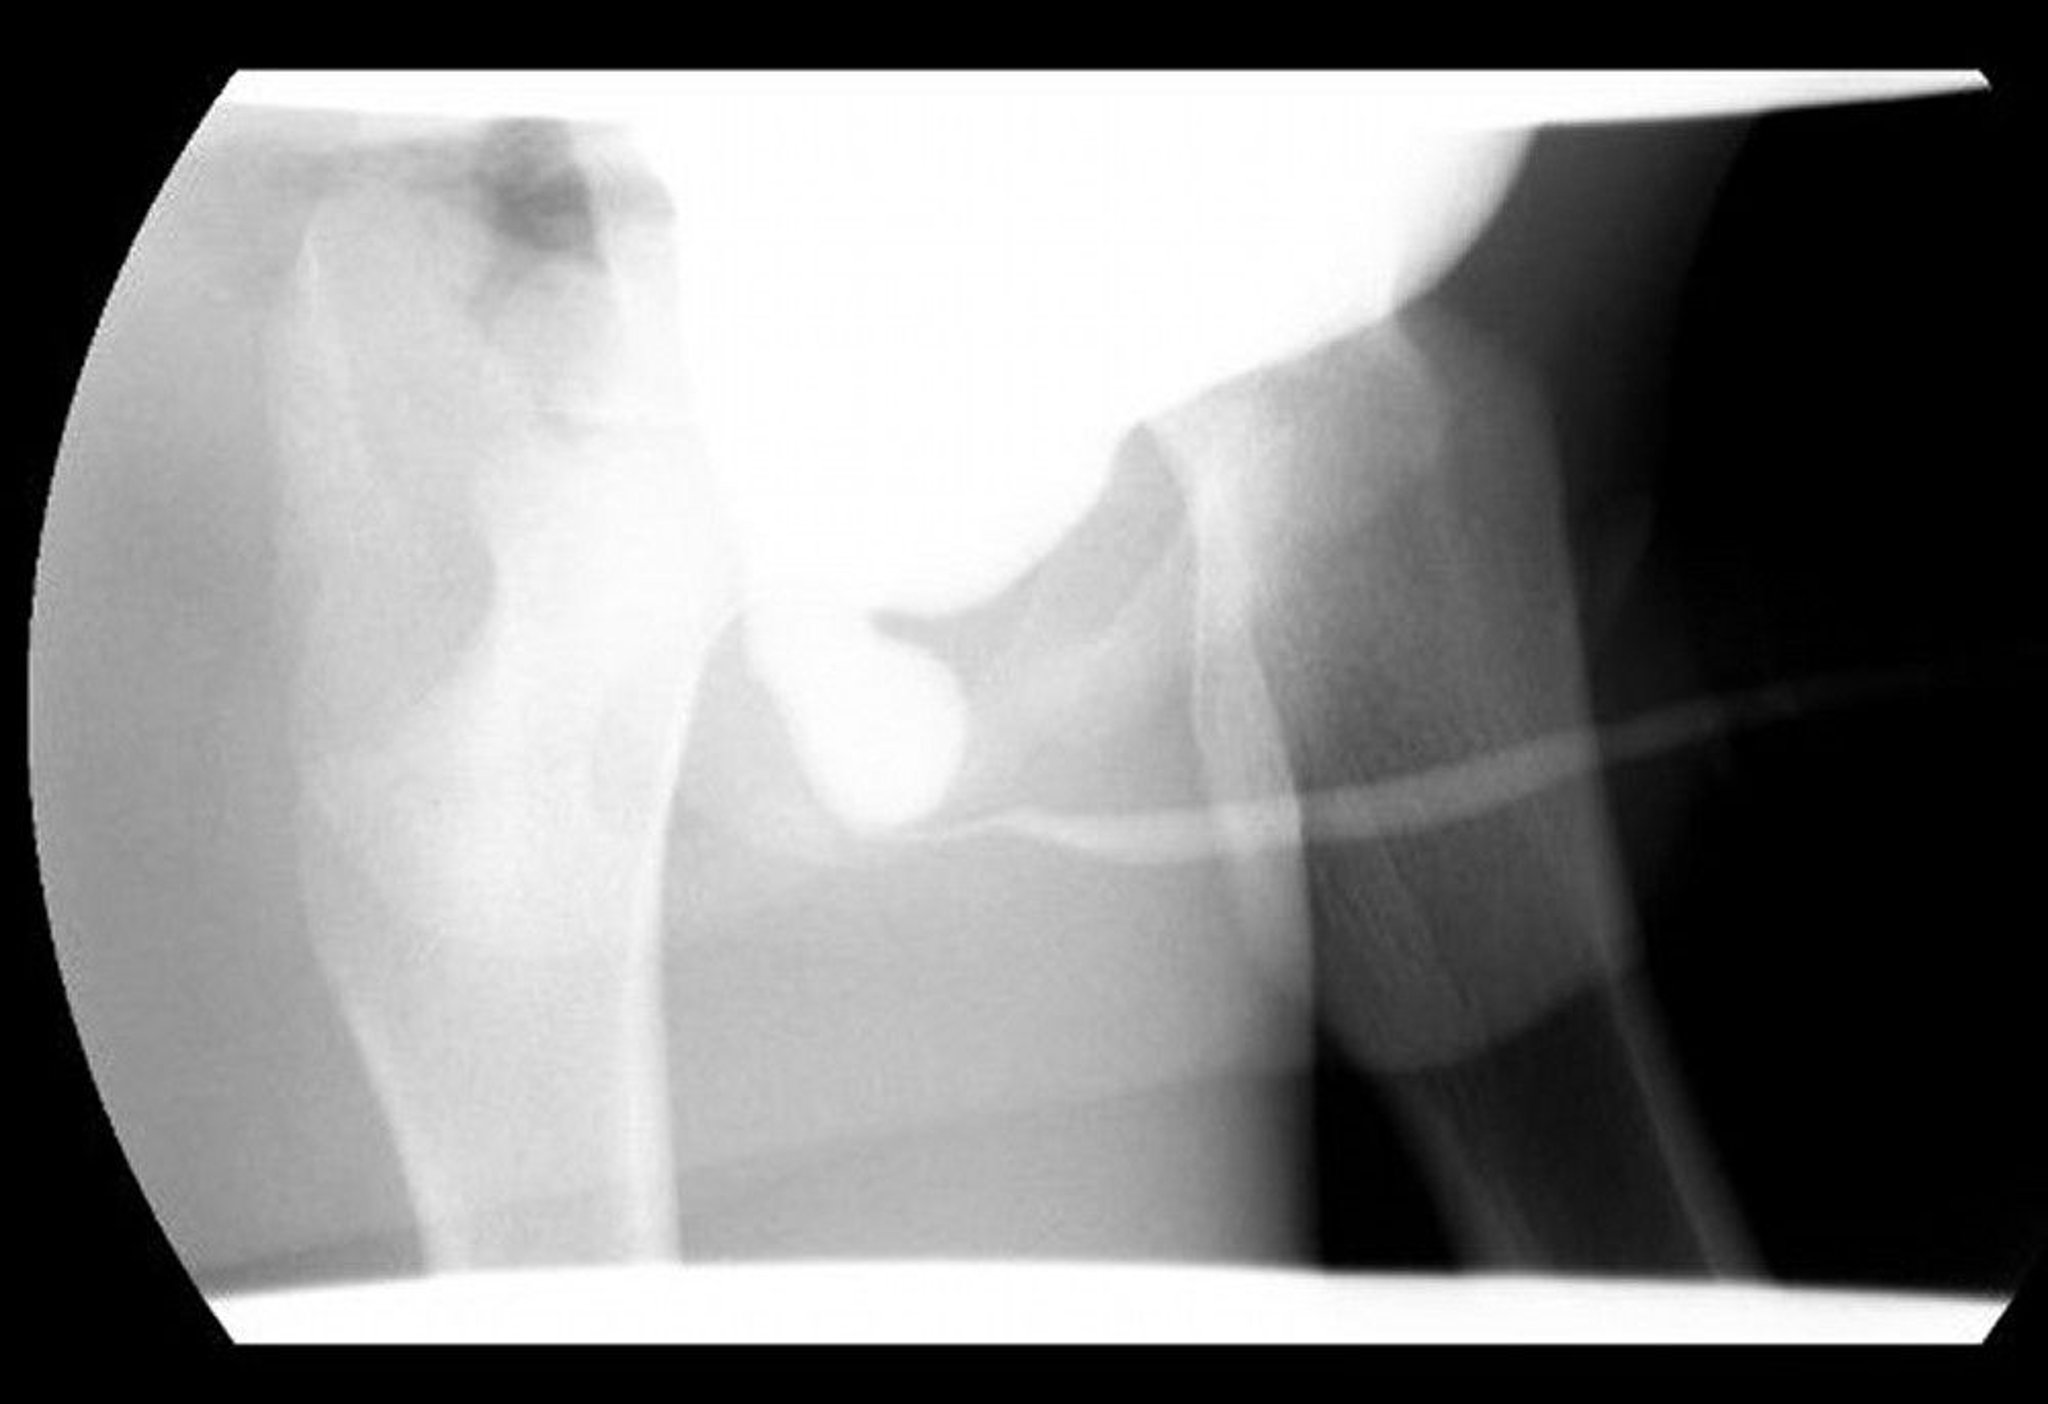

Valvole uretrali posteriori

Questa immagine della cistouretrografia minzionale mostra un'uretra posteriore dilatata con ostruzione distale dovuta alle valvole uretrali posteriori.

Image courtesy of Drs. Ronald Rabinowitz e Jimena Cubillos.